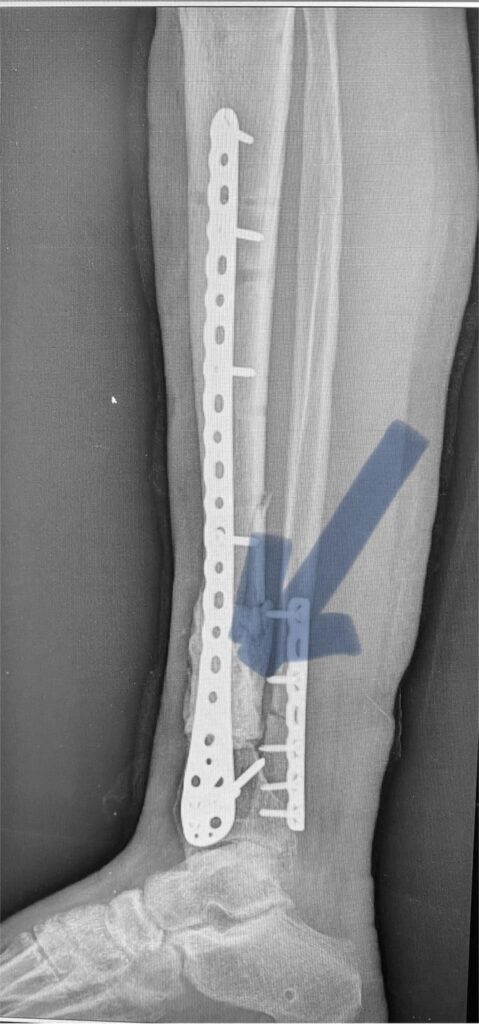

Поэтому вместе с фиксацией этой реально разрушенной плечевой кости (см рентгенограмму) пластиной из минидоступов, мы с Vasyl Parii и Денисом Долгушем не стали одномоментно делать и массивную костную пластику. Взяли ткани снова на посев. Если посев будет стерилен, то следующим этапом сделаем пластику. Если нет, – то вновь проведем антибактериальную мощную терапию.

Затем предстоит вмешательство на плечевом сплетении (есть повреждение). Когда (если) всё пройдет успешно, то вместе с пациентом решим, что делать с плечевым суставом. Скорее всего его замыкание (почти нет дельтовидной мышцы и элементов вращательной манжеты; не знаем объёма восстановления сплетения (положительная динамика есть)).